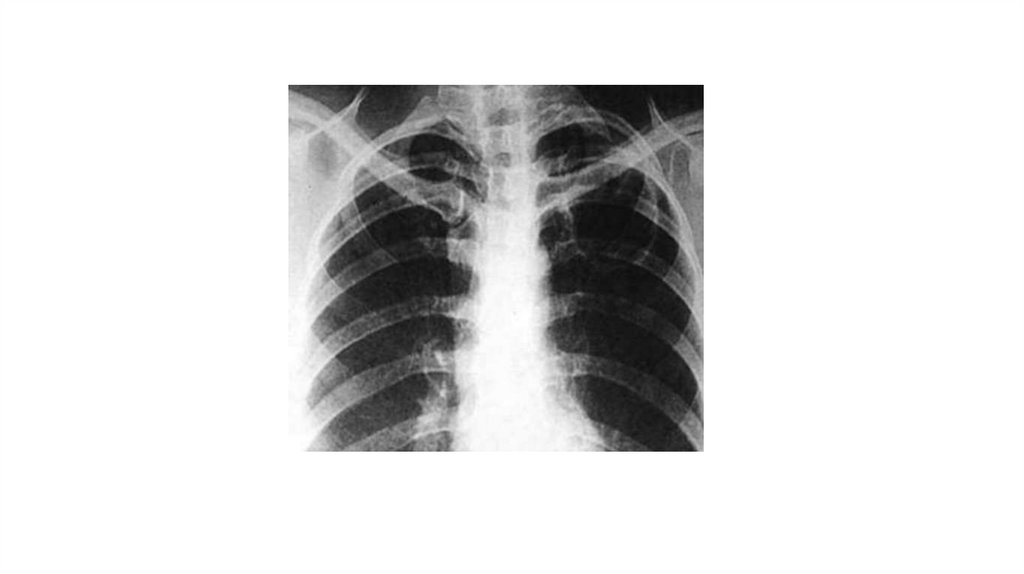

13. Данные инструментальных исследований

РГ ОГК+ТМГ правого легкого:

В С1-2 правого легкого каверна 3 см с толстыми стенками, вокруг и в

нижележащих отделах прежней величины и интенсивности очаги. Левое

легочное поле уменьшено в объеме. В верхних и средних отделах гигантские

каверны на фоне фиброзных изменений. В нижнем отделе (С9) крупный фокус

прежней величины.

Срединная тень смещена влево. Правый синус свободен.

Закл.: ФКТ левого легкого в фазе инфильтрации и стороннего

обсеменения. Практически без динамики.